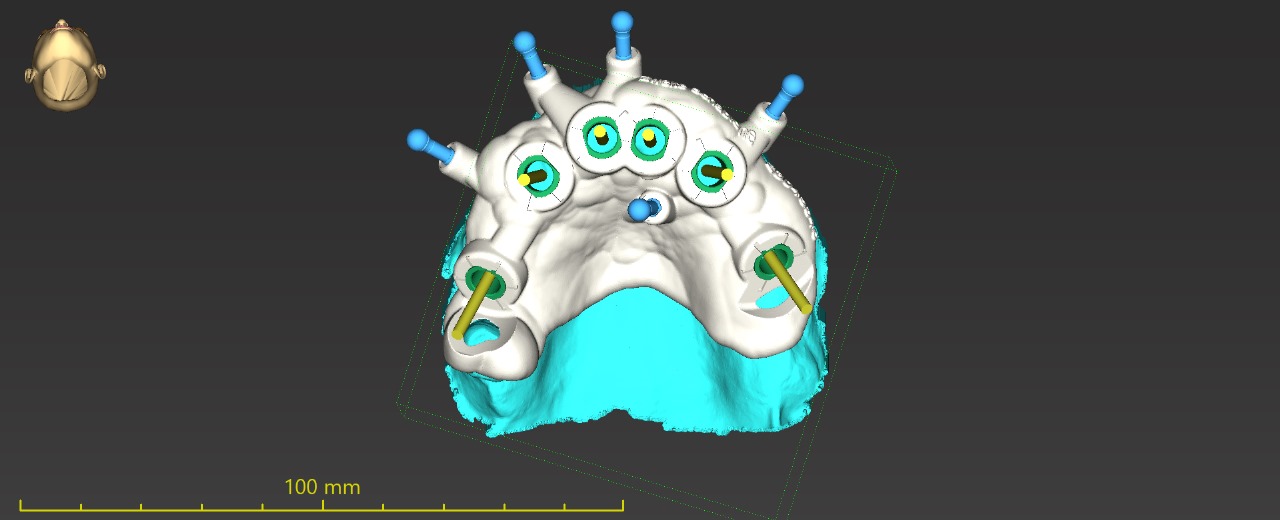

. Surgical guide design ( single sites to stackable full arch guide )

. Falcon guided system ( planning and giide designing )

Upper full arch